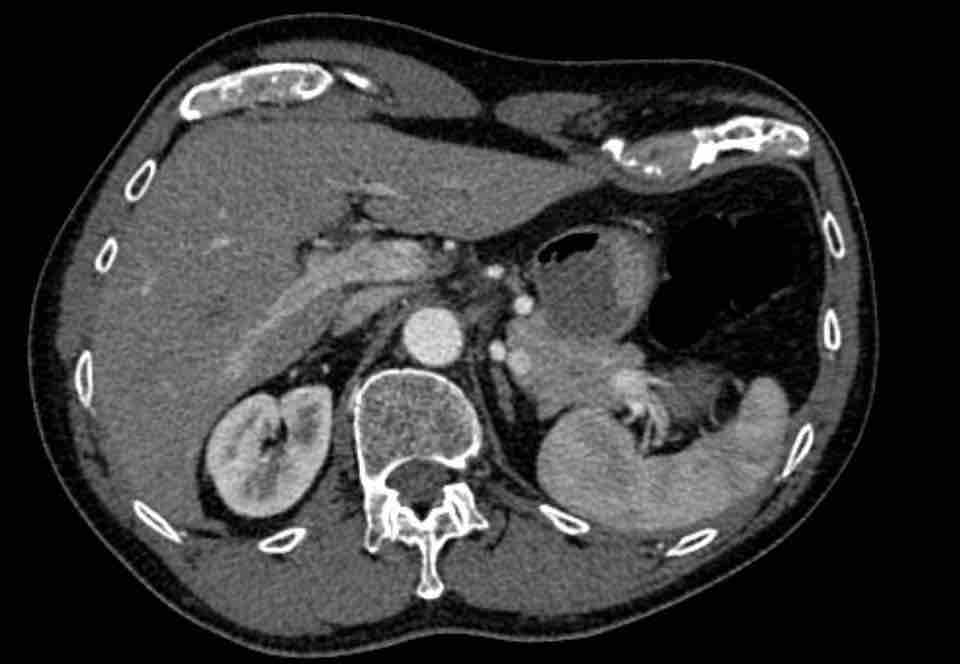

Hình ảnh

Bệnh nhân này được lên kế hoạch cắt thùy trên phải do ung thư phổi và bất thường mạch máu này ban đầu đã bị bỏ sót trên hình ảnh CT.

Những hệ quả trong phẫu thuật của bất thường như vậy nhấn mạnh tầm quan trọng của việc không bỏ sót các biến thể này.